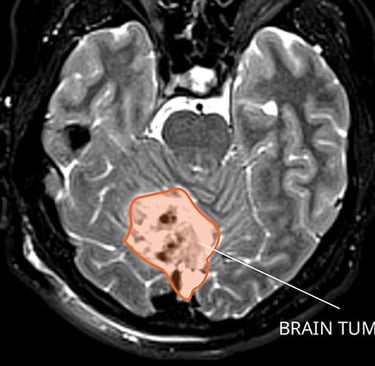

High-grade gliomas are aggressive brain tumors that can strike at any age, but in infants, they have historically carried a grim prognosis—often limiting life expectancy to just two years or less. These tumors grow rapidly in the developing brain, causing symptoms like irritability, vomiting, enlarged head size, and developmental delays.

Dr. Clarke’s research, part of an international collaboration, pinpointed a molecular subgroup of these tumors occurring exclusively in infants under 12 months. This subgroup features distinct genetic markers that make the cancer cells vulnerable to already-approved targeted therapies—drugs originally developed for other cancers.

The study, contributing to a new chapter in the World Health Organization’s classification of brain tumors, involved detailed genomic analysis of infant gliomas. Researchers found that this subgroup lacks the aggressive features seen in older children and adults, responding instead to precision medicines that block specific cancer-driving pathways.